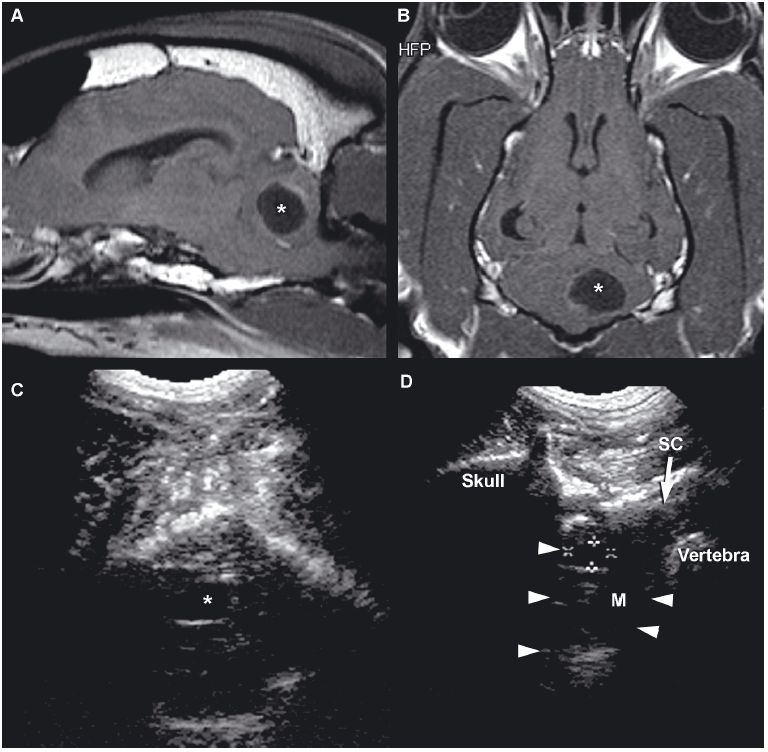

In absence of a fontanel, a lower-frequency transducer (e.g., 5 MHz) can be used to penetrate the skull, enabling partial visualization of the brain. Penetration of the temporal bone can be used for this purpose in some small dogs in which the brain cannot be otherwise imaged (Figure 1.2A).

Visualization of caudal structures of the brain can be achieved by imaging at the foramen magnum (Figure 1.2B).

In most animals with brain neoplasia, MRI or computed tomography is used to make the initial diagnosis because the thick bone of the cranium precludes diagnosis with ultrasonography. Ultrasonography is more likely to be used either intraoperatively or postoperatively, although a window might provided by a persistent fontanel or by bone lysis associated with a neoplasm (Figure 1.13).

In rare instances, a brain abscess or granulomatous mass might occur in either a very young animal or an older animal with a persistent fontanel or other cranial defect (Klopp et al. 2000). Abscessation can appear as a cavitary and hypoechoic lesion containing swirling cellular material compressing the surrounding brain parenchyma (Figure 1.14).

Cystic lesions can be produced by infectious disease or neoplasia or may have no apparent cause (Cruz et al. 2003) (Figure 1.18).

Choroid plexus cysts, intracranial arachnoid cysts, and epidermoid and dermoid cysts associated with the fourth ventricle, quadrigeminal cistern, or cerebellopontine angle have been reported. Arachnoid cysts are seen most commonly in the quadrigeminal cistern, where they appear as a well-defined anechoic mass between the caudal aspect of the cerebral hemispheres. The midbrain will be found ventral to the cyst, and the cerebellum will be caudal (Saito et al. 2001). Congenital cysts secondary to abnormal development or destruction of brain parenchyma, such as in Dandy-Walker syndrome and porencephaly or hydranencephaly, can also occur. Hydranencephaly is diagnosed when the cerebral hemispheres are absent or almost completely absent (Cruz et al. 2003).

Figure 1.18. Cyst in the cerebellum of an 8-year-old terrier. The cyst was drained surgically, but an astrocytoma was later diagnosed at the site (as seen in Figure 1.13). A and B: Sagittal and dorsal postcontrast T1-weighted images of the brain on which a well-defined, hypointense cystlike lesion is identified (*). C: Transverse sonogram of the cerebellum imaged from the foramen magnum on which the cyst appears as a well-defined, oval, anechoic lesion (*). D: Longitudinal sonogram of the cyst. The bone of the skull and vertebral column prevents visualization of portions of the brain and spine, but the part of the brain (arrowheads) can be seen through the foramen magnum. A portion of the spinal cord (SC) can also be observed as it joins the medulla oblongata (M) rostrally. Cursors have been placed to measure the cyst in the cerebellum. Images courtesy of D. Penninck and S. Hecht. E and F: Sonograms of a 1-year-old Chihuahua with hydrocephalus and a quadrigeminal cyst. E: Sagittal sonogram showing the quadrigeminal cyst (Q) and confluence of the dilated lateral ventricles (LV). F: Transverse sonogram. LLV, left lateral ventricle; M, midbrain; and RLV, right lateral ventricle. Images courtesy of B. Poteet, Gulf Coast Veterinary Specialists, Houston.